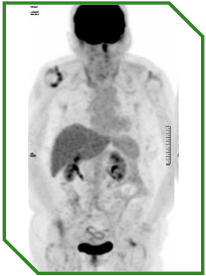

Paciente masculino de 74 anos com carcinoma espinocelular de cabeça e pescoço recorrente/metastático (R/M HNSCC) de orofaringe em base de língua, p16 positivo, previamente tratado com cirurgia extensa e radioquimioterapia adjuvante. Apresentava recidiva metastática predominantemente cutânea, alta expressão de PD‑L1 (CPS 60), ECOG‑PS 2 e limitações clínicas e geriátricas que restringiam a utilização de quimioterapia sistêmica. Diante desse contexto, foi selecionada imunoterapia isolada como estratégia de primeira linha no cenário metastático.